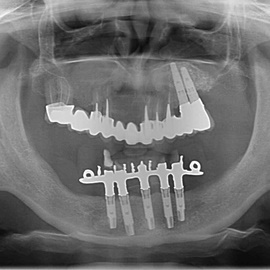

Pacjent z długą historią leczenia implantologicznego. Pierwsze implanty w pozycjach 23, 24 miał wkręcane w Warszawie przed 25 laty. Implant w pozycji górnego prawego kła ma agresywny gwint, ponieważ bezpośrednio po implantacji był obciążony (immediate loading) tymczasowym atachmentem ball abutmentv do stabilizacji tymczasowej protezy ruchomej. Kość szczęki regenerowana i odbudowywana etapami w całym górnym prawym kwadrancie. Pacjent planuje uzupełnić brakujące zęby 25, 26.